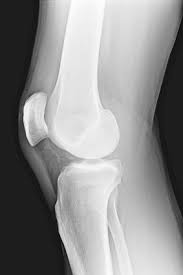

Knee X Ray Image. Skyline view of knee x ray is done to assess the patellofemoral joint alignment. Skyline views are done by flexing the knee keeping the detector perpendicular to the long axis of the limb.

The patella or kneecap is seen sitting in front and to the left of the femur. A lateral view x ray shows the knee from the side. The image here is a front to back view of the knee joint also called the ap view.

Skyline view of knee x ray.